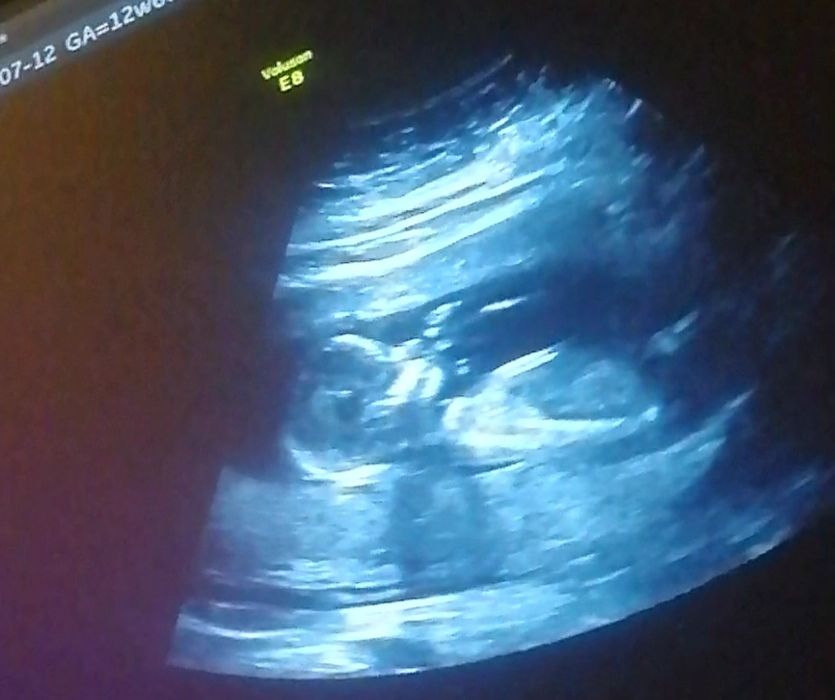

На узи в 14 недель сказали , что мальчик , а я так надеялась на девочку . Уже точно пацан ? фото так

Похоже на мальчика:) вроде:)

Мне все таки кажется, что мальчик. У дочери по крайней мере не так было на УЗИ(насколько я помню😁)Но я бы ещё подождала до 17-18 недель хотя бы.

Не очень понятно по фото 😂

Ксения, вот и мне не понятно 🤷‍♀️

Очень интересно, но ничего не понятно xD

Kris Ivanova, мне тоже не понятно , будем ждать 20ти недель :)